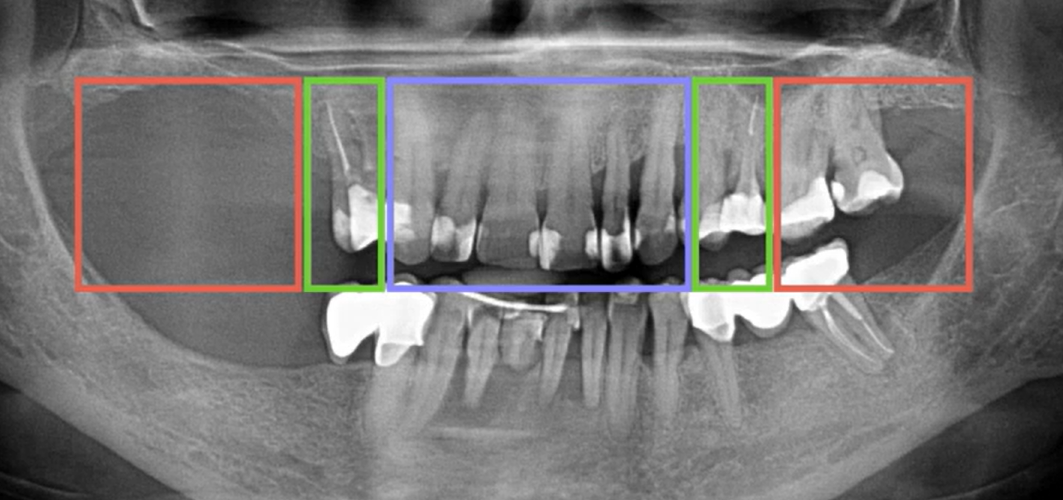

Conventionally, three zones of analysis can be distinguished, see the picture below:

Conditional distribution of control zones and analysis of bone tissue condition YouTube/ Dr. Sergey Rozhnov /sergiodontologist

- Frontal section – highlighted in blue

- Masticatory group – highlighted in red

- Canine-premolar group – highlighted in green

The image above shows an uneven alveolar ridge in the anterior region, as well as a noticeable bone deficiency in the masticatory zone of the first quadrant. This means that after tooth extraction, a bone reduction in the anterior region will be necessary.

The image above shows a typical scenario. Preliminary analysis is critical for protocols with a limited number of implants.